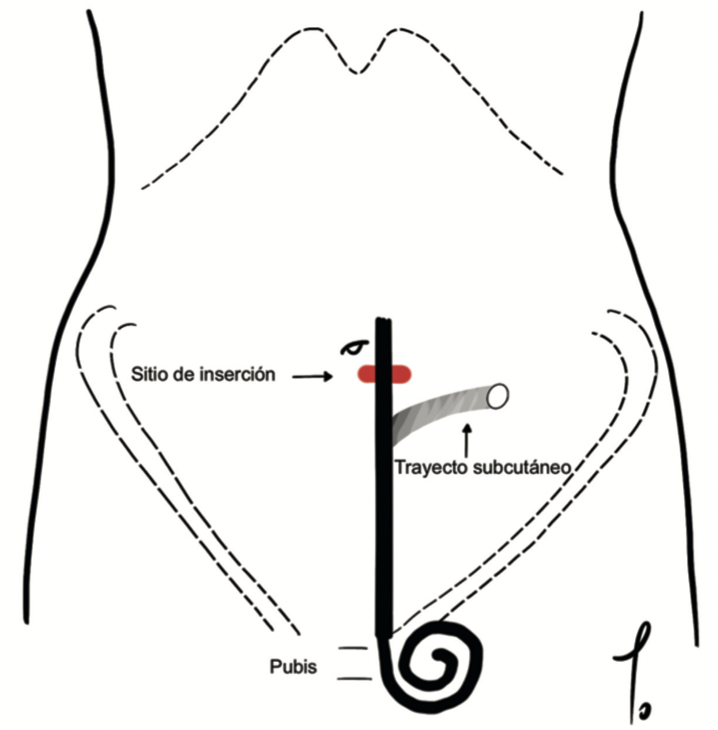

Tomás González Arestizábal, Constanza Dictter, Paulina Abara, Vicente Villegas, Catalina Torres, Antonella Sanguineti

|

|

|